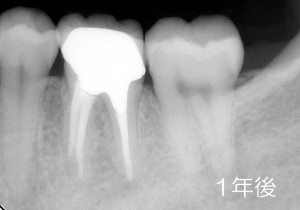

1年後がこちら

その後は、その他の治療も終わり、今日に至るまで3ヶ月毎の定期検診と歯石取り&クリーニングを行っております。